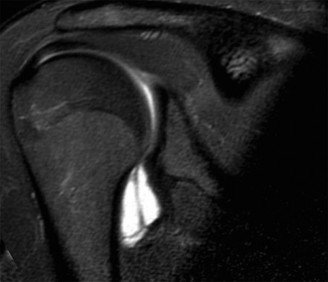

The correct answer is (A). In a young patient, the most likely injury associated with a glenohumeral dislocation is a labral tear (see Fig. 2–31). In an older patient, >40 years old, a rotator cuff tear is more likely. Other possible associated injuries include:

Figure 2–31 MRA demonstrating an anterior labral tear.